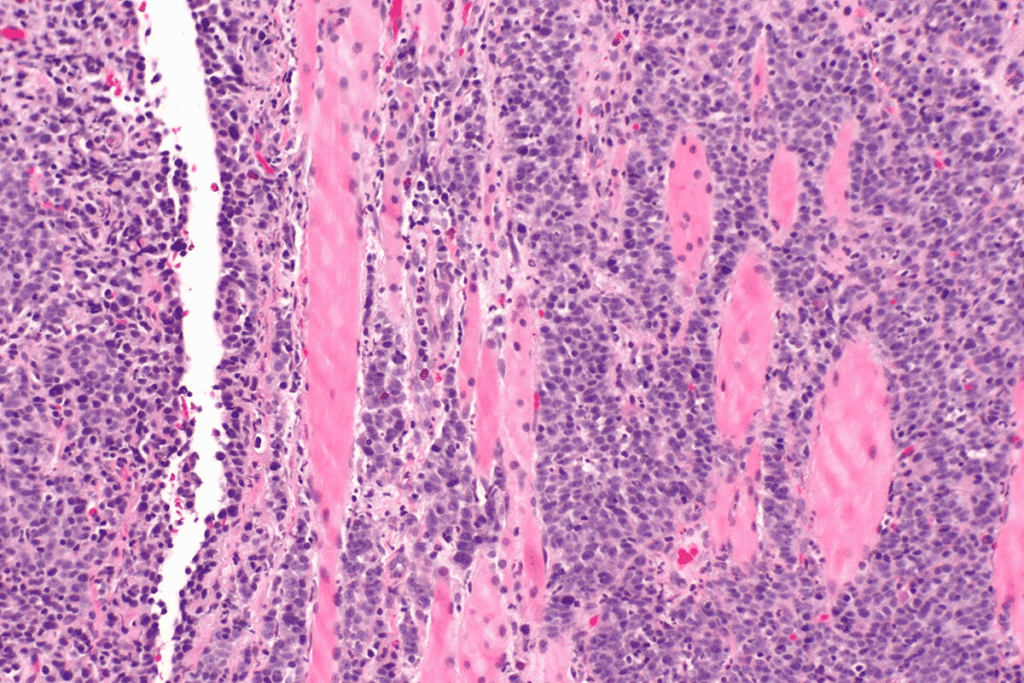

Histopathological Evaluation and Markers

After getting a biopsy sample, it’s examined under a microscope. This helps find signs of SCC, like abnormal cell growth and keratinization.

Doctors also look at the tumor’s thickness, how far it has spread, and if it has high-risk features. These details help stage the cancer and predict its outcome.